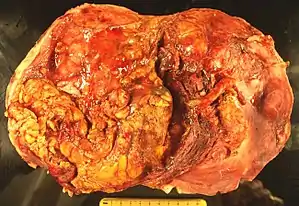

MTSCC has a gross appearance close to papillary RCC. Microscopically, it has three histologic components: mucin, tumor cells forming tubules, and spindle cells. It is characterized by the proliferation of cuboidal and spindle cells arranged in tubular or sheet-like arrays, typically with a mucinous or myxoid background.